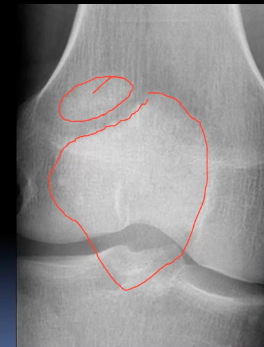

This 75 year old woman presented with difficulty walking and knee pain. How would you describe these X-rays?